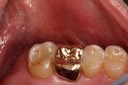

Photos of Clinical Operations

Drs. Peter Kearney, Terry McKay, John St. Germain, and Laurie Vanzella - Mentors